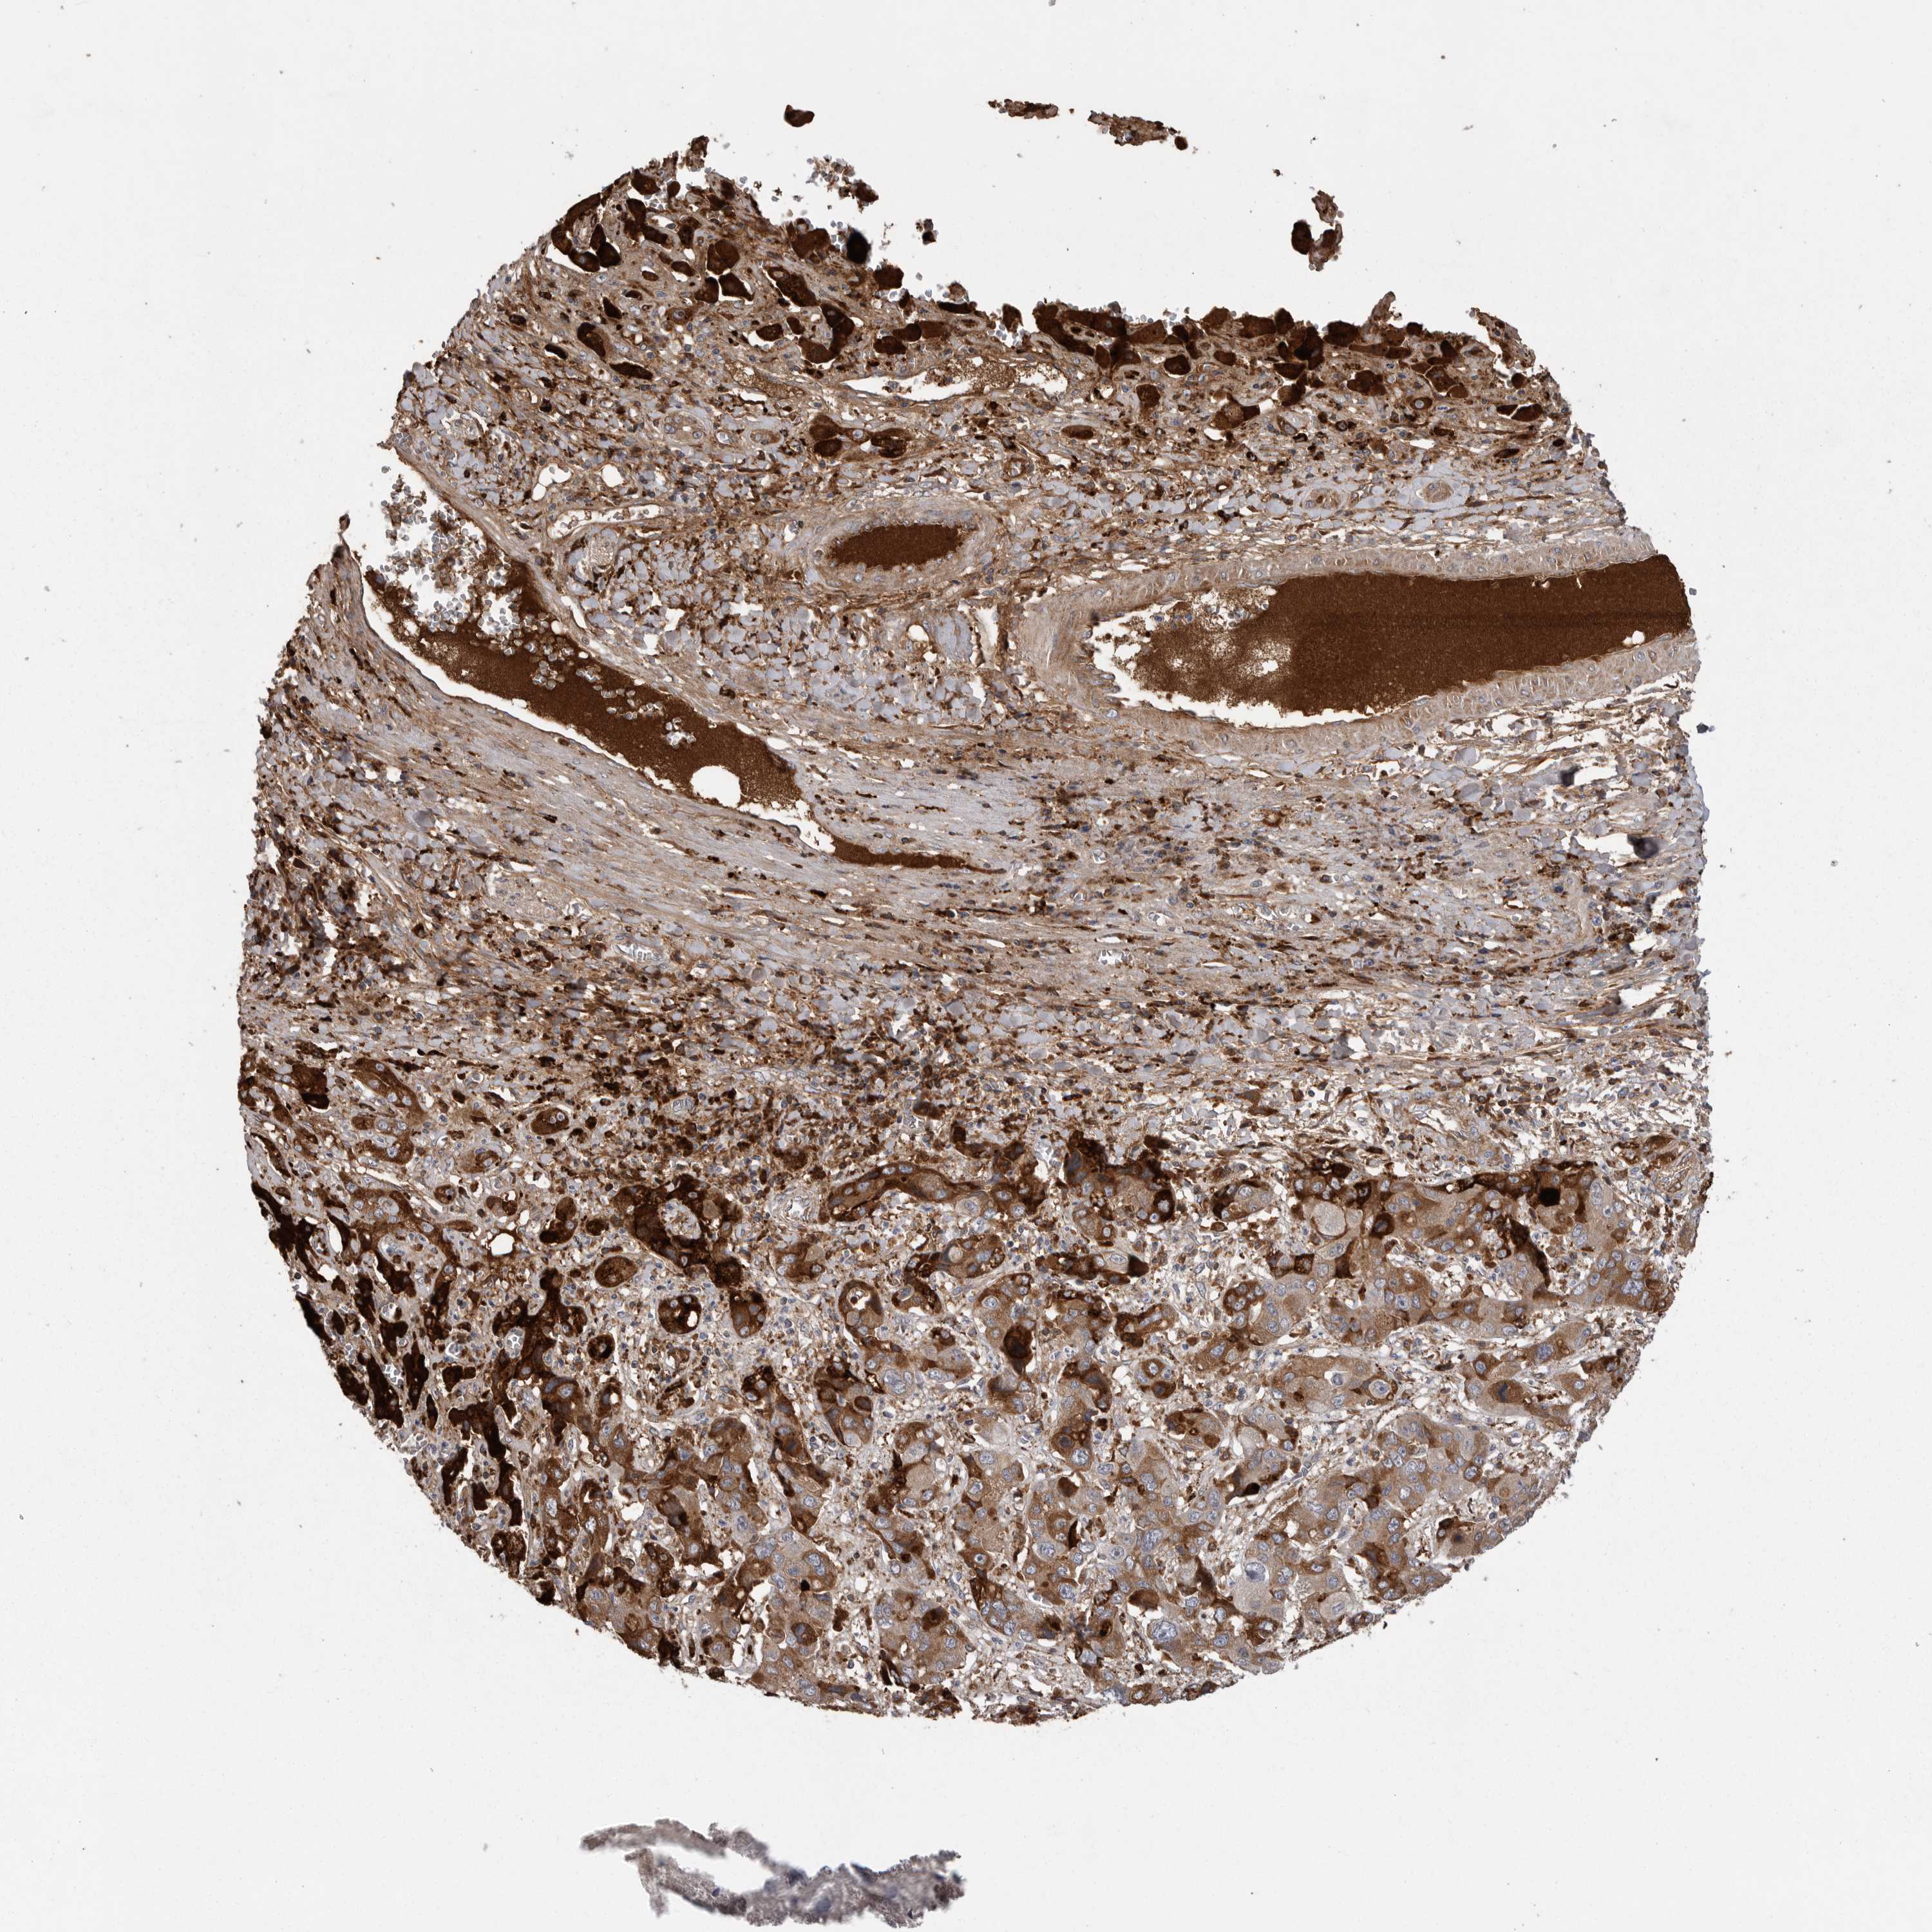

LIVER CANCER - Protein expressioni

A mouse-over function shows sample information and annotation data. Click on an image to view it in a full screen mode. Samples can be filtered based on level of antibody staining by selecting one or several of the following categories: high, medium, low and not detected. The assay and annotation is described here.

Note that samples used for immunohistochemistry by the Human Protein Atlas do not correspond to samples in the TCGA dataset.

Antibody stainingi

Antibody staining in the annotated cell types in the current human tissue is reported as not detected, low, medium, or high, based on conventional immunohistochemistry profiling in selected tissues. This score is based on the combination of the staining intensity and fraction of stained cells.

Each image is clickable and will lead to virtual microscopy that enables deeper exploration of all samples and also displays staining intensity scores, fraction scores and subcellular localization as well as patient and tissue information for each sample.

Antibody HPA027367

Antibody HPA027396

Antibody CAB005036

Staining

Cholangiocarcinoma

Carcinoma, Hepatocellular, NOS